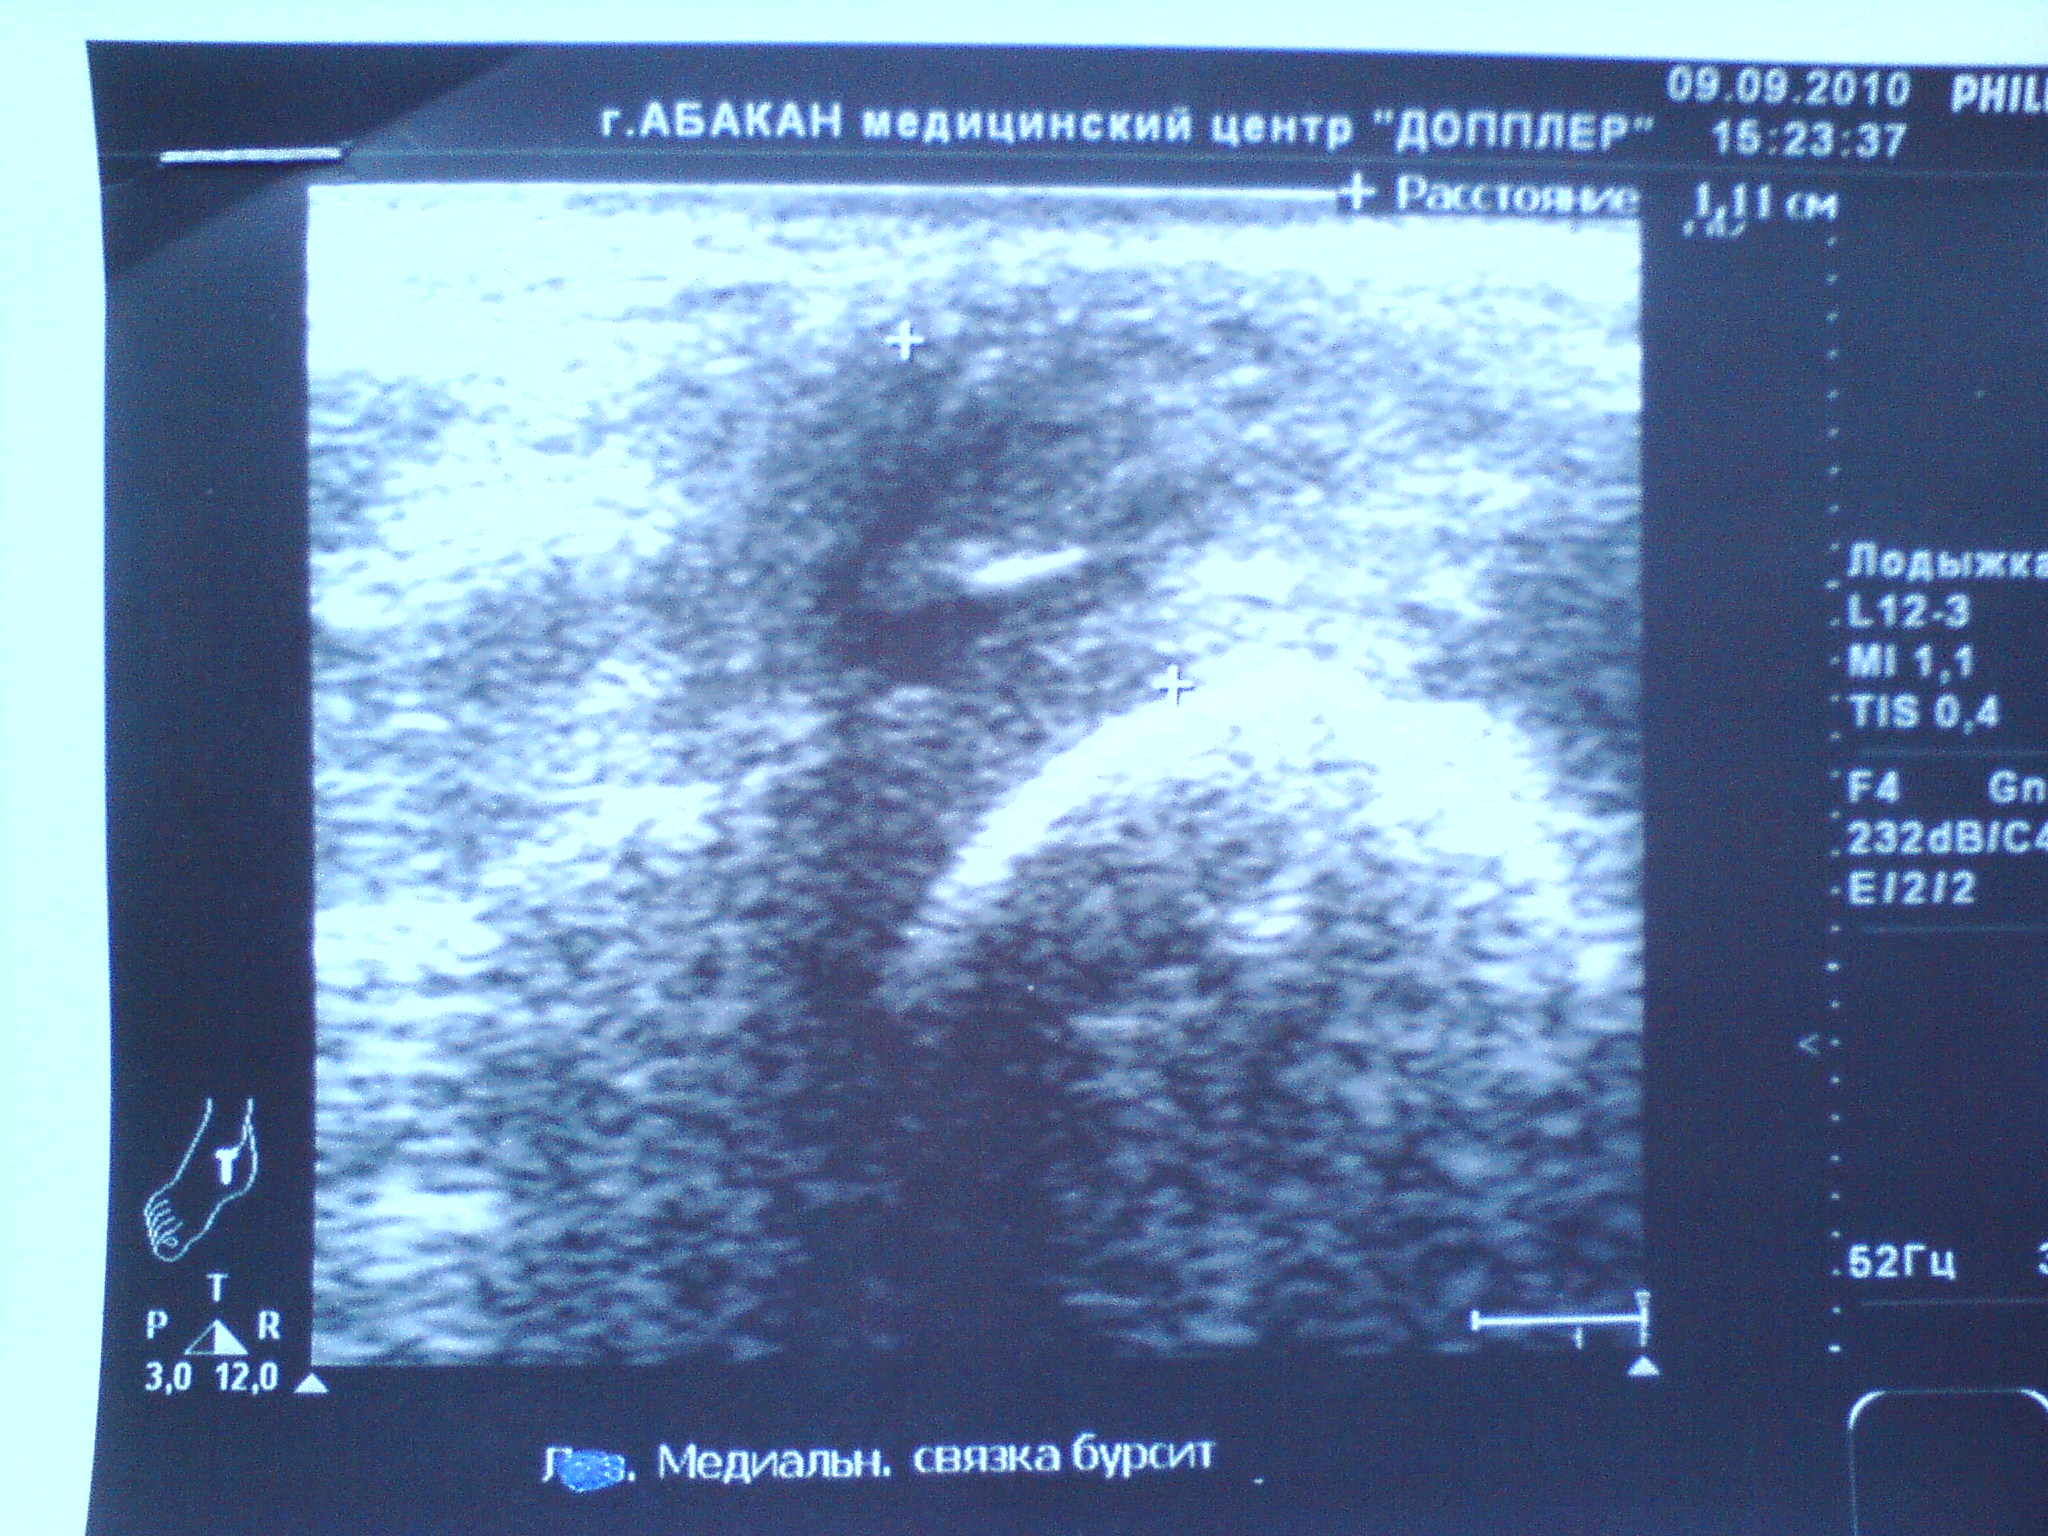

Начну с того что проходил службу в армии с декабря 2008-декабрь 2009 года. Примерно в Июле 2009 года ударили по правой ноге в область голени. В армии этот случай хотел "замять" поэтому ходил с больной ногой. В сан части сказал что подвернул ногу. Как выяснилось после демобилизации (6 месяцев спустя) был перелом малой берцовой кости. Этот диагноз поставили в местном травмпункте, где сделали снимок голени. Снимок я прикрепил. Примерно через неделю после удара я заступал в караул с спрыгивал с кузова грузового автомобиля и видимо преземлился неудачно, т.к. сразу же упал на руки от резкой боли в правой ноге. После этого голеностоп еще больше начал болеть. К сожалению в сан часть я так и не обратился. Так и ходил хромал.Вот уже на протяжении года у меня дискомфорт при ходьбе (чувство натянутости в голеностопе), а также были ночью боли в голеностопном суставе. Появилось чувство деформированности стопы. Дома хожу в мягких тапочках. Очень быстро утомляюсь. Бегать не могу в походы не хожу хотя раньше занимался туризмом. Уже спустя больше 1 года и 2 месяца обратился в травматологическую клинику, где сделали снимок голеностопного сустава и поставили диагноз перелома заднего отростка таранной кости. Ничего не назначали для лечения, Затем я снова обратился в трав пункт нашего города сделали УЗИ и там мне поставили диагноз застарелого разрыва дельтовидной связки, и направили на операцию на ее подшитие, после осмотра глав врачом он сказал что тоже перелом в суставе бал и операцию делать не будут. Затем я уже ездил в город Новосибирск и обратился в областную больницу где поставили диагноз "Неконсолидированного перелома суставного отростка таранной кости и прописал лечение ФИзио таблетки "структум", "мовалис". (прикрепил листок). Контрольная явка через 3 месяца.Пролечился 1 месяц ушло чувство стянутости в голени, чему я рад, но теперь стали болеть связки в голеностопе, а также все равно что мурашки в области пятки, Что делать?

Я считаю что лучше много сказать, чем потом выяснять долгое время. Я постараюсь сделать что вы рекомендуете! Однако прикрепил еще результат узи.